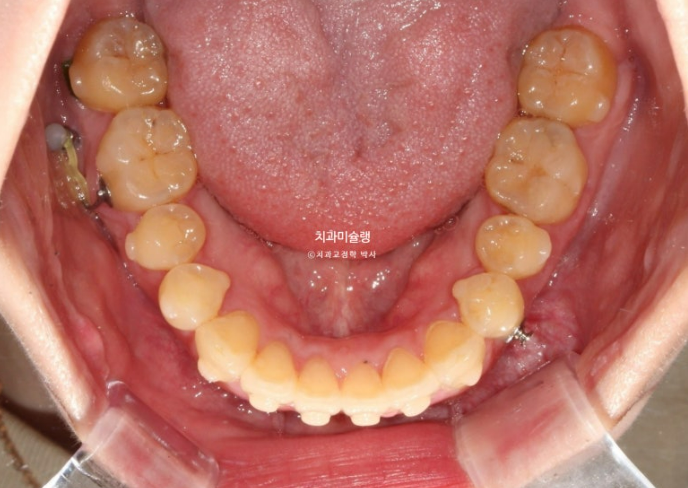

25년 6월, 1년간 첫세트의 50개 장치를 모두 낀 후 모습입니다.

25.06

중심선이 아직 어긋나 있지만 개방교합은 해소가 되었습니다.

교합관계는 1급이지만 어금니 교합이 약간 떠있습니다.

배열은 좋습니다.

미진한 부분을 바로잡고자 추가장치 재제작에 들어갑니다.

25년 5월부터 11월까지 20개 장치를 모두 낀 후 치료를 마무리 했습니다.

25.11

추가장치 이후 이제 중심선은 잘 맞습니다.

어금니 교합은 물샐틈 없는 1급 교합관계를 보입니다.